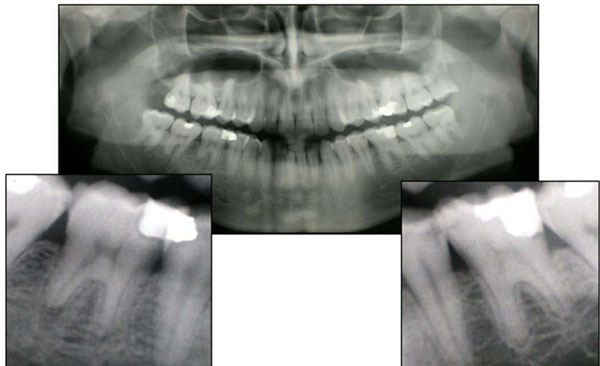

The first case studied concerns a 24 year old male who was experiencing pain in the first mandibular molars (36 and 46) which had been restored, but affected by secondary caries (Fig. 1).

Case 1. The ortopantomograph shows left and right first inferior molars (3.6-4.6) with secondary decay.

He sought dental center where an orthopantomograph was taken, followed by root canal therapy, and restorations of both teeth. At the end of treatment, which lasted for about 4 months, persistent pain, particularly in tooth 36, and widespread throughout the left side of the mandible, prompted the patient to seek out another dental practice where another orthopantomograph was taken and periapical lesions correlated to excessive extrusion of endodontic material beyond the apical region were diagnosed in both treated dental elements (Fig. 2). There was an associated mandibular swelling and a associated fistula deep abscess fistula of tooth 36. Because of the amount of extruded material, the second dentist deemed the extraction of 36 necessary, and decided to start an orthograde retreatment of 46. Tooth 36 was exported followed by alveolar curettage of the periradicular bone and orthograde endodontic retreatment of tooth 46. Further treatment included the insertion of an osseointegrated implant to replace tooth 36, in light of the young age of the patient.

Case 1. The second opg shows the excessive extrusion of endodontic material beyond the apical region and the incomplete obturation of the canals.